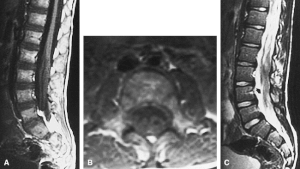

| MRI compatible with Dejerine-Sottas type spinal nerve enlargement | |

On medical imaging, the nerves of the extremities (and cranial nerves in some cases) appear enlarged due to hypertrophy of the connective interstitial tissue, giving the nerves a distinct "onion-bulb" appearance. Peripheral (and possibly cranial) nerve excitability and conduction speed are reduced.[1]